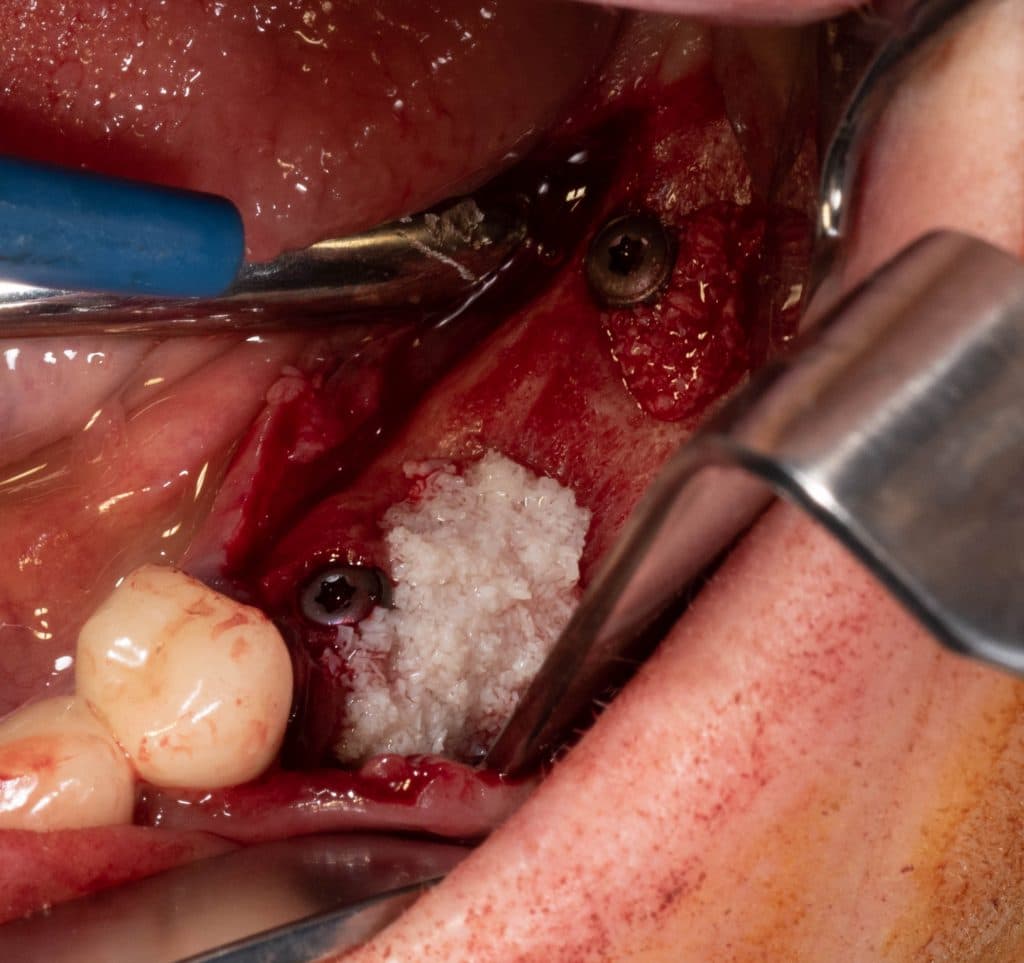

Horizontal GBR with Bioss

Bio-gide fixed with pins